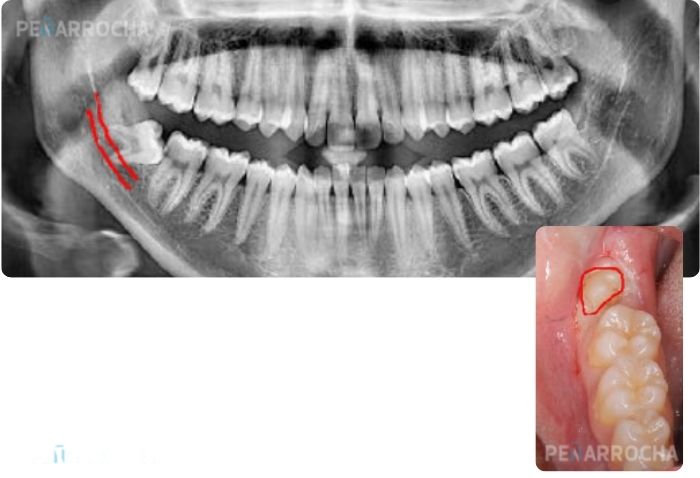

La evaluación se realiza mediante una exploración clínica y una ortopantomografía o TAC para conocer la relación del molar con estructuras vecinas, como el nervio dentario inferior.

Estos dientes suelen aparecer entre los 17 y 25 años, y si no lo hacen de forma correcta, pueden quedar parcialmente expuestos, facilitando la acumulación bacteriana y aumentando el riesgo de pericoronaritis e infecciones crónicas.

- Infecciones recurrentes o pericoronaritis.